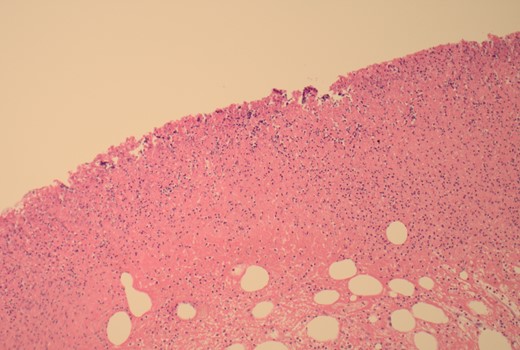

100× magnification showing the ulcerated surface of the lipoma which is covered by fibrin and neutrophils. The clear cystic spaces below this are the residual fat cells.

100× magnification of the lipoma illustrating the adipocytes which show cytoplasmic distention by optically clear fat.